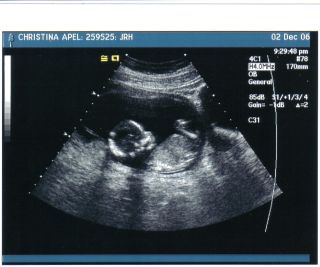

I'm back But i had alittle scary. I was spotting but it was nothing thank god. I just have alittle ireation in there. SO they just want me to take it easy. Baby is fine and healthy. She was trying to see if she could tell what it is she said it might be a but she thinks that it is the umbical cord was in the way. But is ok cause i get another on in a week to see what the sex is. Here is some pics of the baby. There is one that is so cute that it has it arms behind it head and knees are up. I see it on the seen moving around jumping and moving it arms legs. It was so cute. Image Attachment(s):